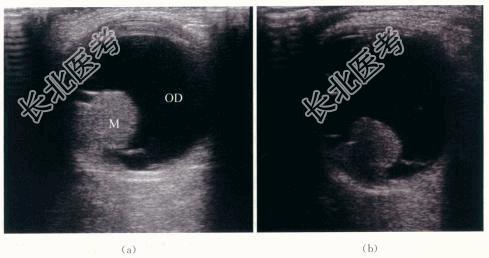

- [材料题] 患者,男性,52岁,因“右眼视力逐渐下降半年.眼前黑影伴视物变形1周”就诊。体格检查:患者视野检查示蓝色视野缺损大于红色视野缺损。特殊检查:眼底检查示右眼玻璃体混浊。颞侧可见脉络膜实性隆起,呈棕褐色,表面有出血。隆起物周边视网膜呈青灰色隆起。影像资料如下: